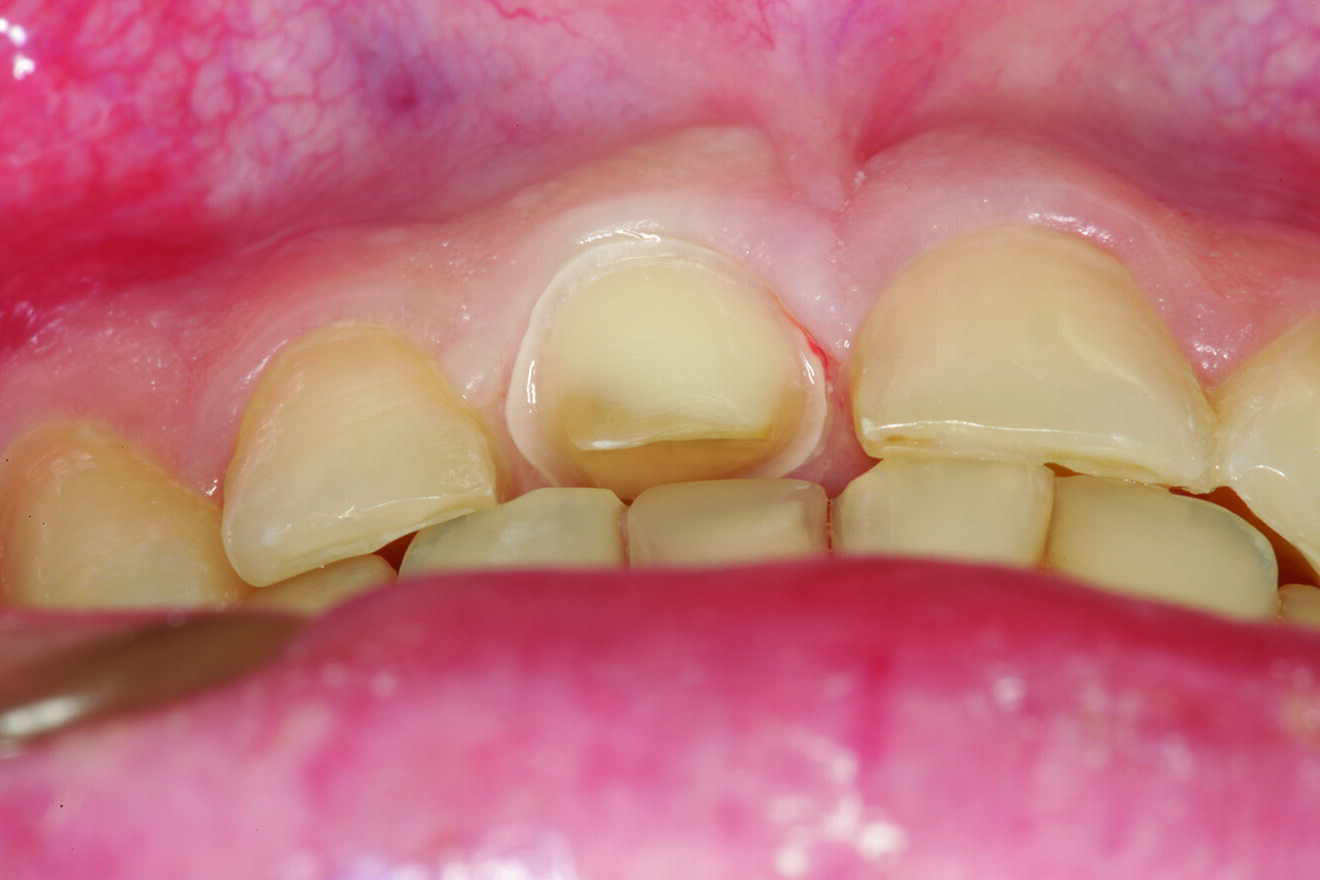

Fig. 3: Incisal view showing that tooth #41 was the arch form’s most facially positioned mandibular incisor.

What about the alignment of the opposing teeth? It could be observed that excessive wear was present on the incisal edges of teeth #31 and 41 (Fig. 2). From the incisal view, exten­sive wear was seen on all mandibular inci­sal edges due to occlusal disease—which is often seen yet left untreated (Fig. 3). Tooth #41 was also facially positioned so that in pro­trusive excursion it engaged the palatal surface of tooth #11 prematurely, placing addi­tional stress on both the palatal surface and inci­sal edge of tooth #11 before coupling with the remainder of the maxillary anterior segment. This demonstrates that addressing these issues restoratively involves more than just fixing a chipped composite restoration.